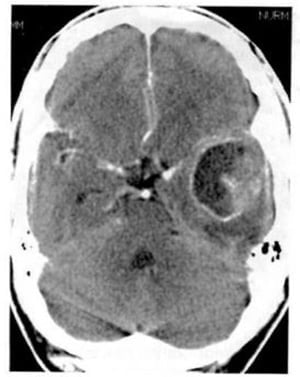

1.2. U nguyên bào đệm đa dạng (Hình 1.32)

Dấu hiệu XQCLĐT:

– U ở chất trắng trên lều, với đặc trưng là hoại tử, xuất huyết, phù nguồn gốc mạch máu, hiệu ứng choán chỗ, không đồng nhất, bắt chất cản quang đáng kể.

Hình 1.32. U nguyên bào đệm đa dạng. Hình ảnh trước tiêm (a) là tổn thương mật độ thấp ở hai bên đường giữa. Ở thùy trán bên trái còn có một tổn thương mật độ cao (xuất huyết). Sau tiêm (b), bắt chất cản quang mạnh, dạng viền.